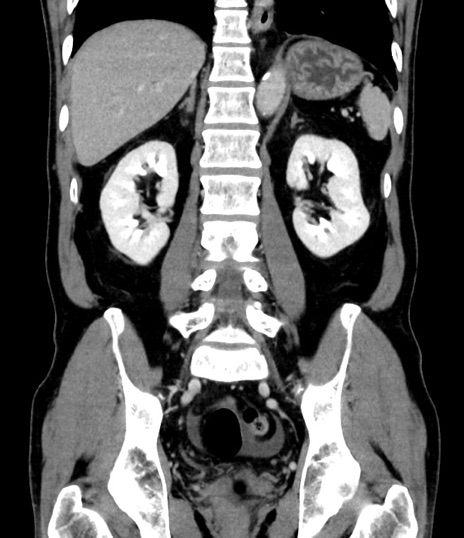

症例

横断像